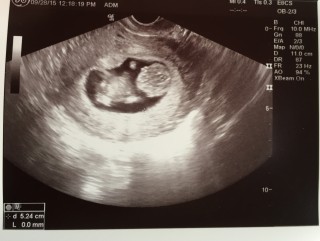

初めてのベビちゃん♪ 5.24cmに成長していました☆ つわりで体重は4㎏落ちたけど、ベビちゃんは順調で安心しました。 手足動かしていて可愛らしかったです♪ 次回は4週間後に検診です☆